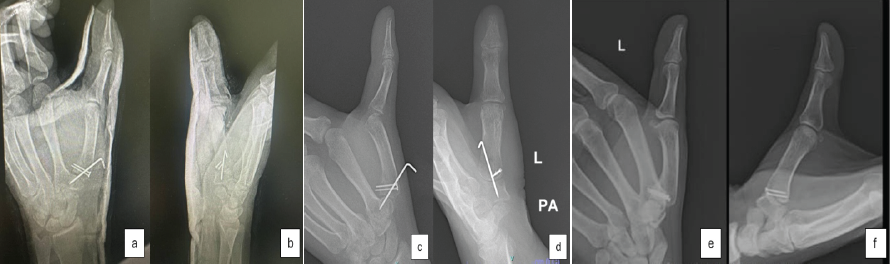

At 12 weeks postoperatively, the patient achieved a full, pain-free range of motion in the thumb (Fig. 4). The functional Kapandji score was 7/10 at the 3-month follow-up, and 10/10 at the end of 10 months reflecting excellent thumb mobility, dexterity, and functional recovery (Fig. 5). The patient achieved good union at fracture site and a congruent joint on radiographs (Fig. 6).

Figure 4: Result at 3 months.

Figure 5: Result at 10 months.

Figure 6: Post-operative radiographs. (a and b) immediate post operative radiographs. (c and d) radiographs at 6 weeks post operative. (e and f) radiographs at 10 months after the surgery.